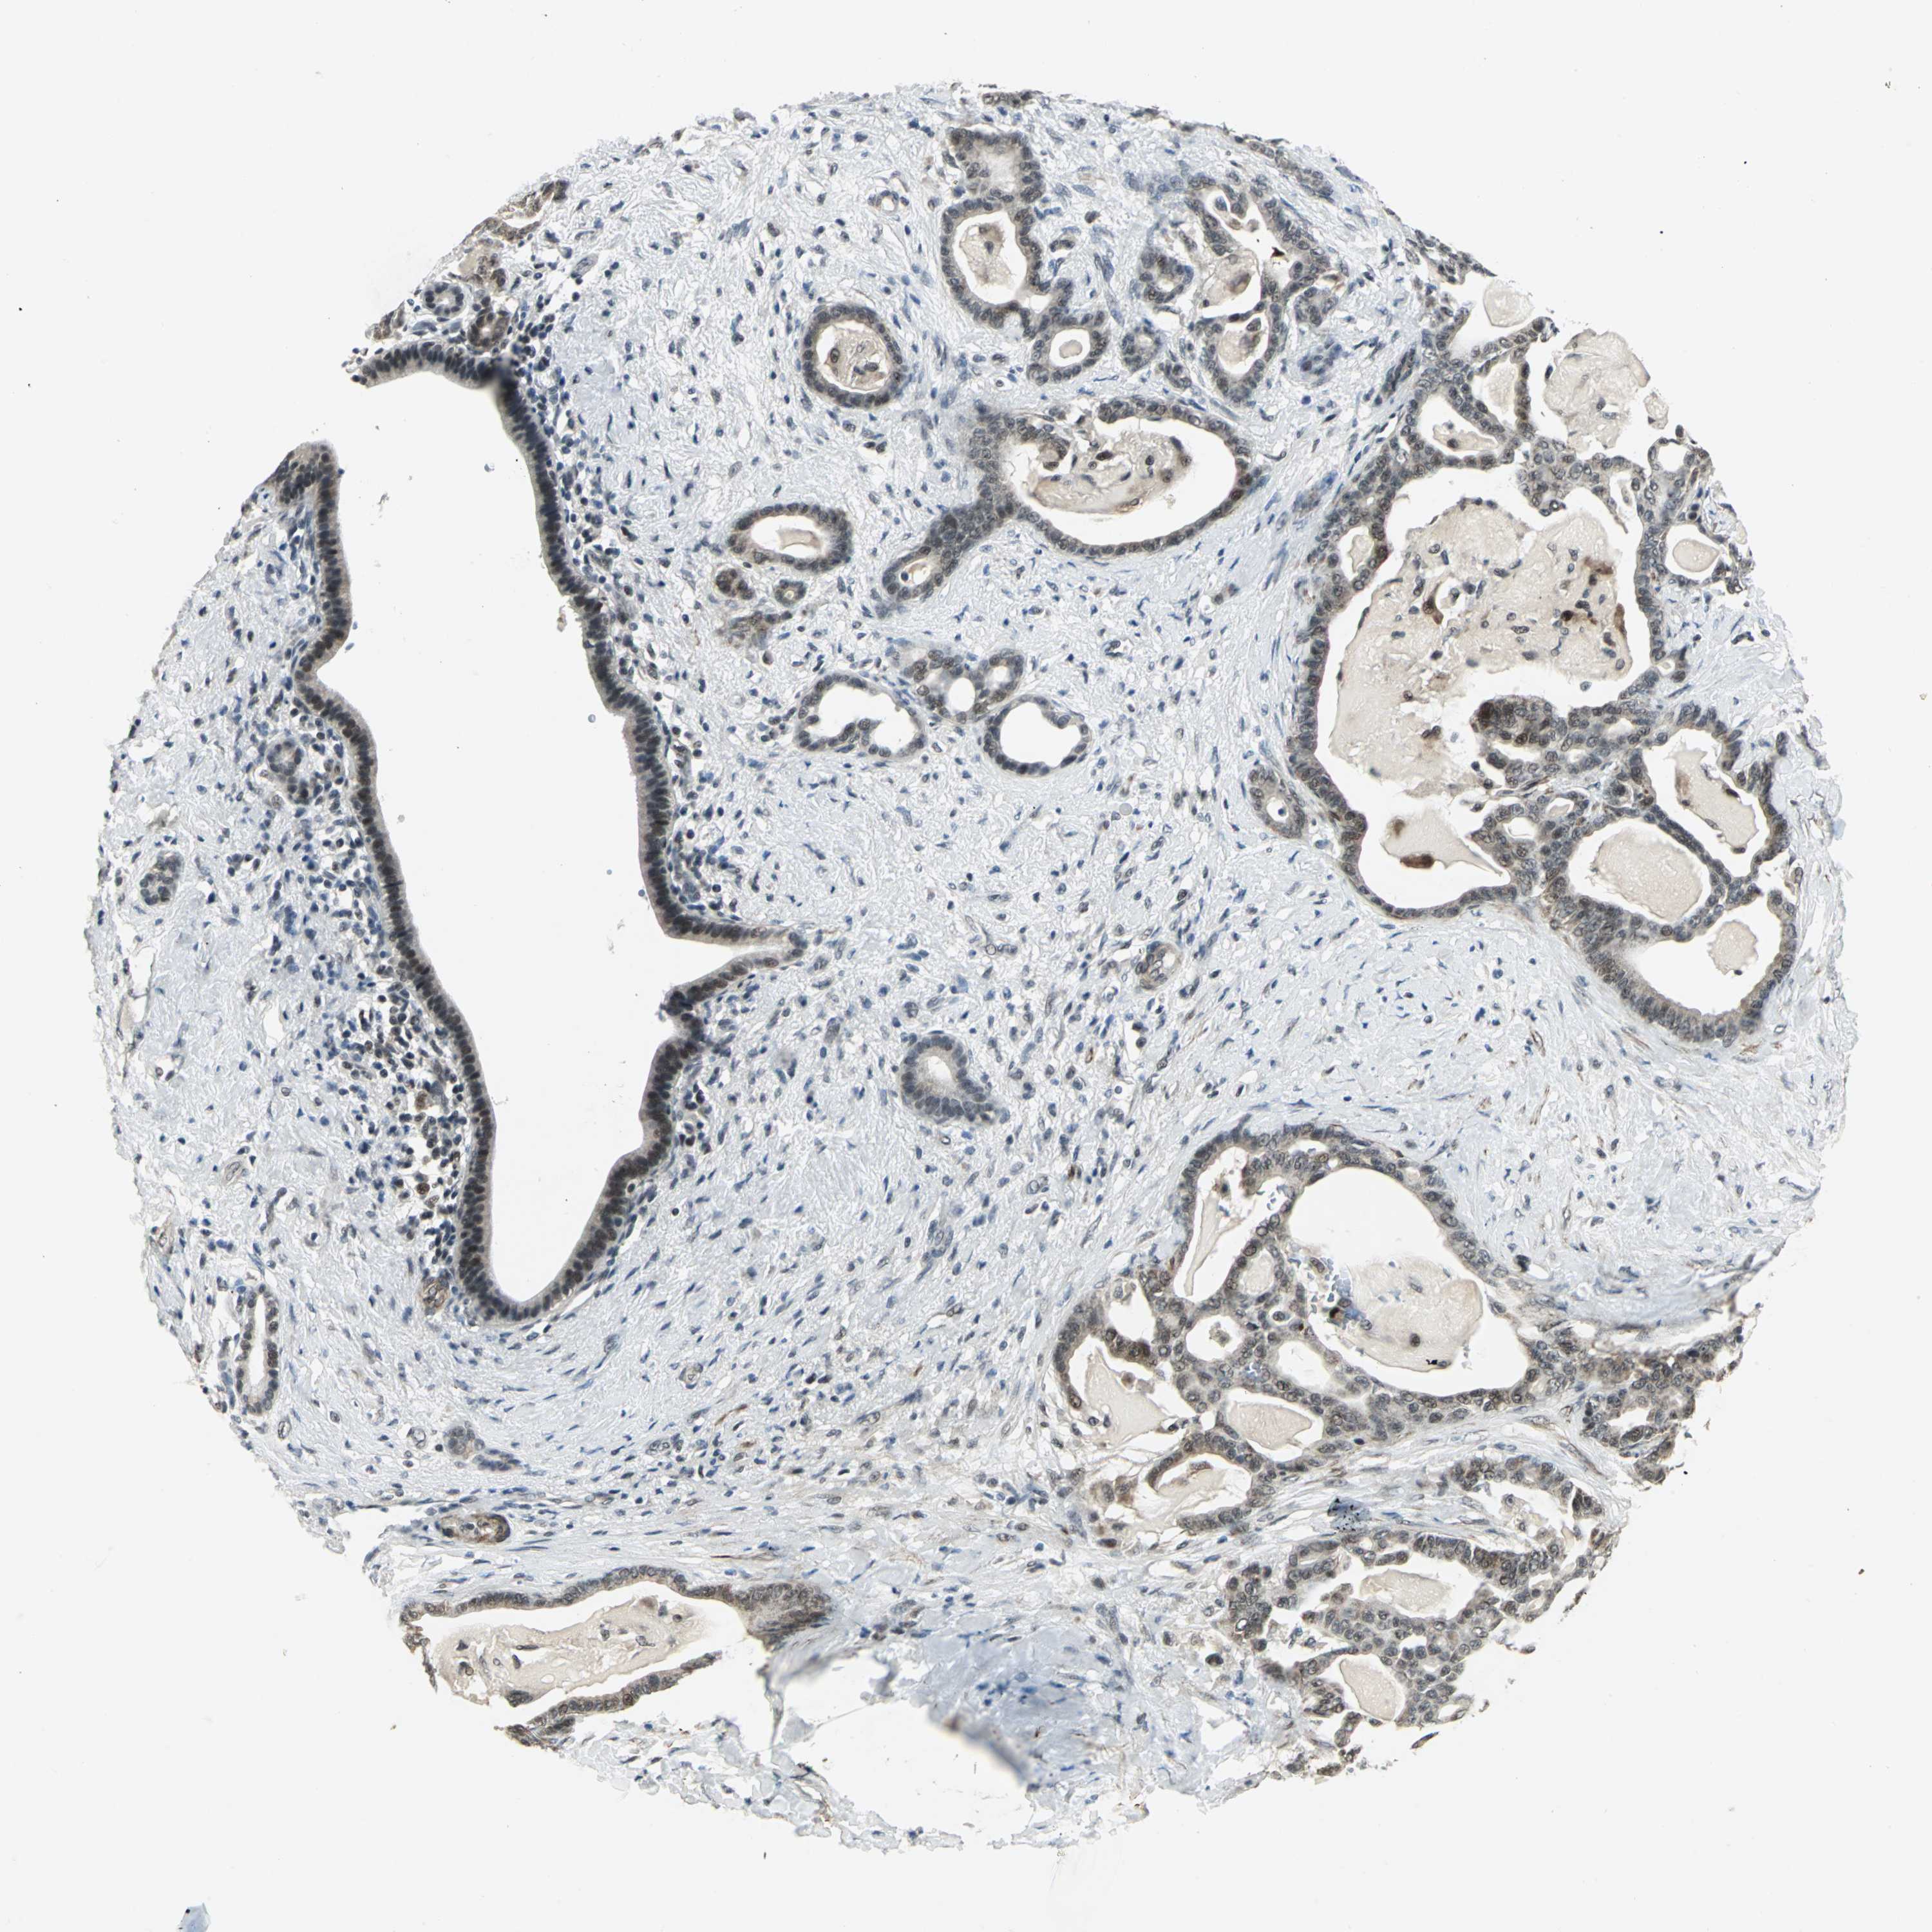

PANCREATIC CANCER - Protein expressioni

A mouse-over function shows sample information and annotation data. Click on an image to view it in a full screen mode. Samples can be filtered based on level of antibody staining by selecting one or several of the following categories: high, medium, low and not detected. The assay and annotation is described here.

Note that samples used for immunohistochemistry by the Human Protein Atlas do not correspond to samples in the TCGA dataset.

Antibody stainingi

Antibody staining in the annotated cell types in the current human tissue is reported as not detected, low, medium, or high, based on conventional immunohistochemistry profiling in selected tissues. This score is based on the combination of the staining intensity and fraction of stained cells.

Each image is clickable and will lead to virtual microscopy that enables deeper exploration of all samples and also displays staining intensity scores, fraction scores and subcellular localization as well as patient and tissue information for each sample.

Antibody HPA005544

Antibody CAB004508

Staining

High

Medium

Low

Not detected

Intensity

Strong

Moderate

Weak

Negative

Quantity

>75%

75%-25%

<25%

None

Location

Nuclear

Cytoplasmic/membranous

Cytoplasmic/membranous,nuclear

Adenocarcinoma, NOS